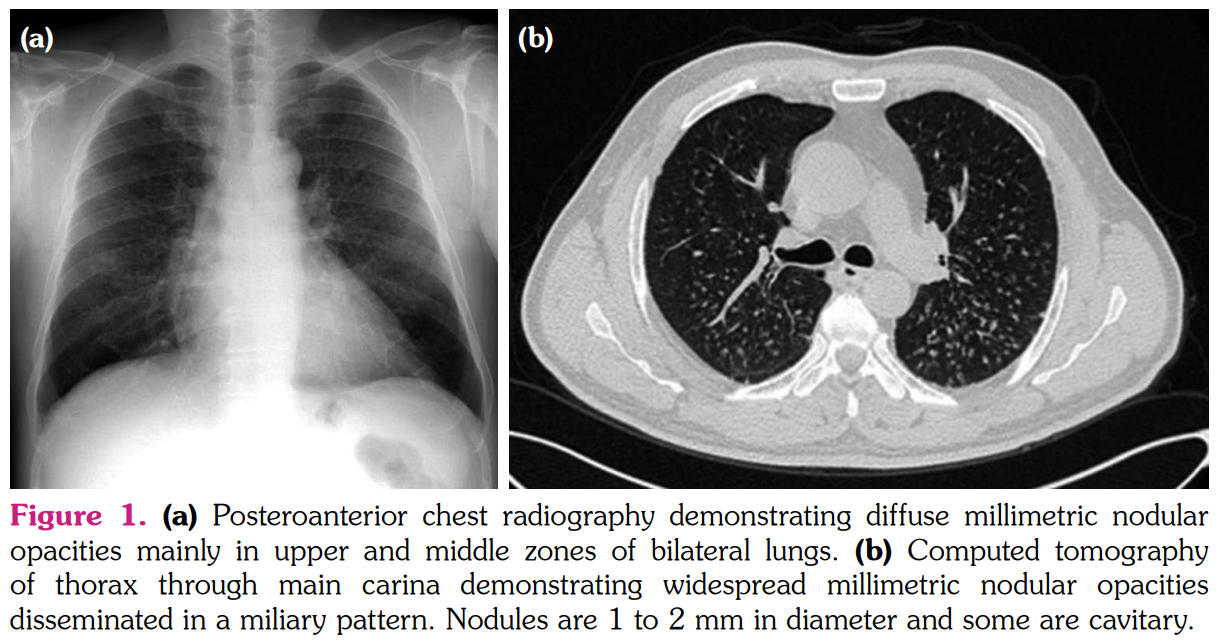

The smears of bronchoalveolar lavage (BAL) were negative for any bacteria, fungi, or acid- fast bacilli. Cytological examination revealed numerous macrophages, few lymphocytes, and few neutrophils. BAL cultures were also negative. Serological tests for the infection of viruses and fungi were negative. The pathological examination of pulmonary wedge resection performed from lingula revealed foreign-body type giant cell reaction and poorly- formed non-caseating granulomas distributed mainly along interlobular septa and subpleural zones (Figure 2). Asteroid bodies as well as a birefringent material were seen in the cytoplasms of giant-cell histiocytes under polarized microscope (Figure 3a, b). Histochemical stains did not reveal any microorganisms and lung tissue cultures were also negative for any mycobacteria species. Based on the clinical, radiological, and pathological findings, a diagnosis of sarcoid-like granulomatous reaction induced by adalimumab was confirmed. Given the lack of radiological response four months after cessation of adalimumab, methylprednisolone 32 mg/day peroral was initiated. The patient was controlled every month initially and every two months thereafter with a gradual reduction in methylprednisolone dosage. At the end of nine months of steroid therapy, a control CT of thorax revealed stable nodular opacities in both lungs. As psoriatic lesions gradually increased and worsened during this period, ustekinumab was started.